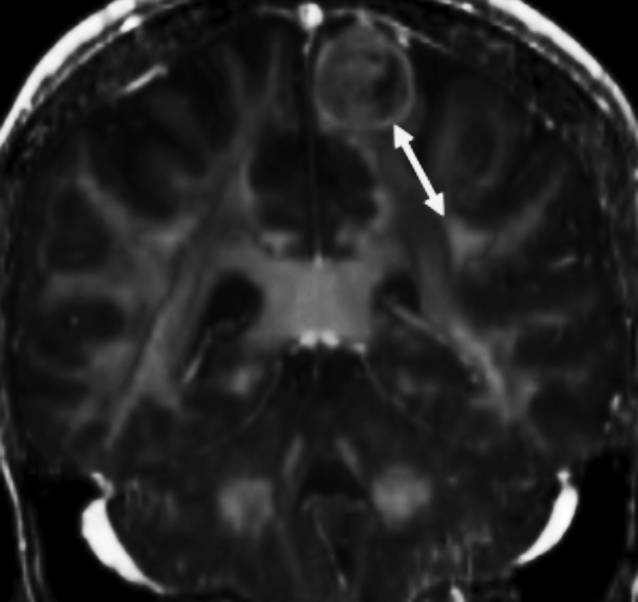

该研究纳入60例成人脑肿瘤患者,包含54个神经胶质瘤、3个脑膜瘤、2个颅内转移瘤和1个胚胎发育不良性神经上皮瘤;术前均行DTI成像扫描。DTI图像显示3个主要白质纤维束传导通路:上纵束(SLF)、扣带和皮质脊髓束;并且测量病灶至各个通路的最短LTD(图1)。同时,从电子病历中收集患者术后神经功能障碍发生率和死亡率。

图1. MRI-T2加权冠状位成像中,白色箭头表示肿瘤病灶至上纵束间的最短距离(LTD)。